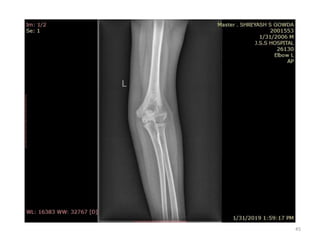

Elbow joint

• Secondary ossification Centres : (3 bones; 6 Ocs)

Capitulum (C) - appearance - 1 year of life

Head of Radius (R)– appearance -4 to 5 years

Medial Epicondyle (ME)

Appearance – 5 to 6 years

Fusion – 16 to 17 years

Trochlea (T) – appearance – 9 to 11 years

Olecranon Process of Ulna (OP)

Appearance - 8 to 9 years

Fusion- 16-17 years

Lateral Epicondyle(LE) – 11 to 12 years

Conjoint (Composite)Epiphysis (CE) [fusion of C+T+LE]

Formation – 14 to 16 years

Fusion – 16-17 years

Note: Fusion of O.Centres at elbow joint is 16-17 years in male, 15-16 years in female